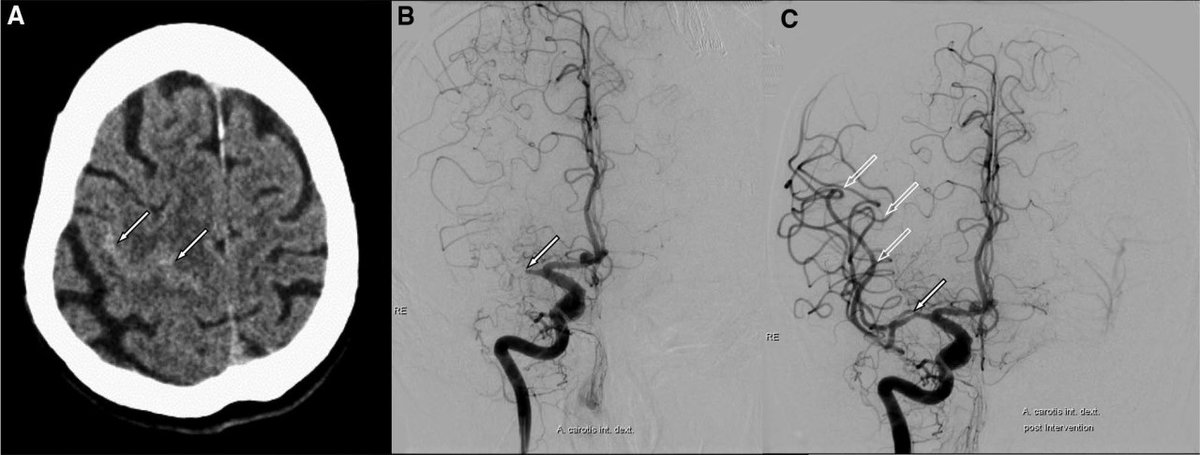

Stroke AHA/ASA on Twitter: "Stroke Images: Convexal subarachnoid ...